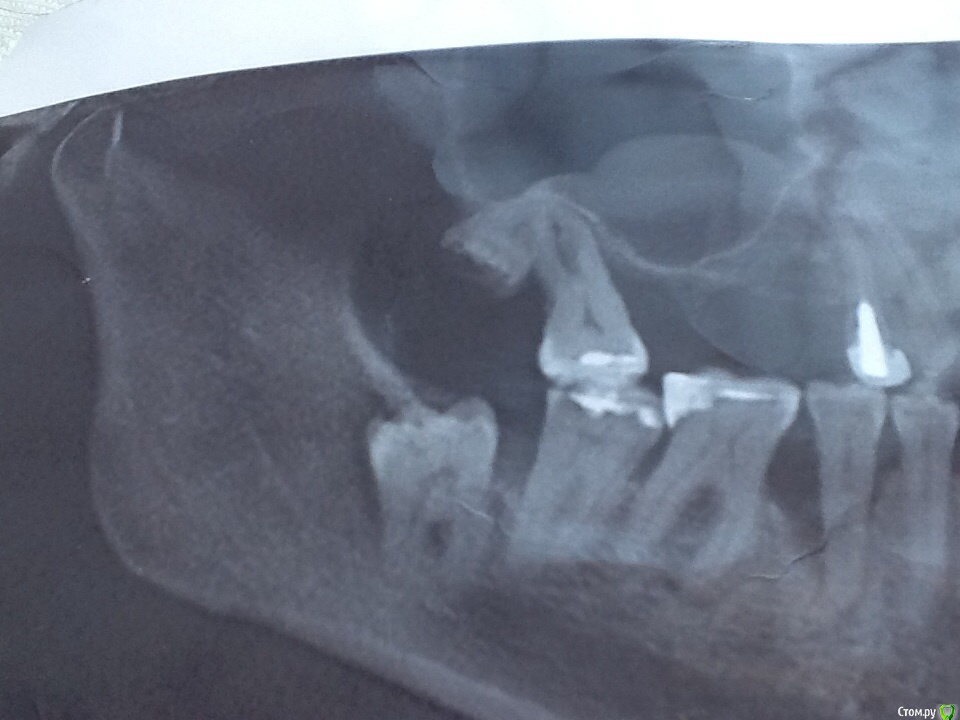

NoSpane Опубликовано 27 марта, 2017 Поделиться Опубликовано 27 марта, 2017 Добрый день, уважаемые доктора! Нужен ваш профессиональный совет касательно удаления всех ( ?! ) зубов мудрости и проблем с оставшимися жевательными зубами. Прокомментируйте, пожалуйста, весь снимок - что и как нужно делать! Хотелось бы сохранить хотя бы нижние " семерки" , но местные стоматологи соглашаются только на вариант удаление 7,8 в паре либо просто не берутся . По поводу верхней челюсти тоже разноречивые мнения - парно удалять, либо вначале 7, потом 8. В случае перфорации пазухи тоже разделились во мнениях- КАК ушивать и ушивать ли вообще Удалять по частям не хотят, предлагают целиком дергать Хотя сразу же мельком обмолвились, что не гарантируют сохранность челюсти при таком удалении Ходила-ходила по врачам, только время потеряла - в итоге полная неразбериха в голове Одинаковых мнений у врачей нет и какому специалисту довериться я не знаю Помогите, пожалуйста, определиться!!! Буду благодарна за любое мнение! Ссылка на комментарий

St. Опубликовано 28 марта, 2017 Поделиться Опубликовано 28 марта, 2017 Да оставьте в покое 7, не надо их ни депульпировать профилактически, ни удалять. Если не берутся у Вас, едьте в больший город, ищите доктора который возьмется.8 я бы рекомендовала удалить все 4. И да, после удалений лунку обычно ушивают.Еще по этому снимку есть проблемы с десной и другими зубами. Ссылка на комментарий

St. Опубликовано 29 марта, 2017 Поделиться Опубликовано 29 марта, 2017 У Вас на всех зубах уходит кость, и под десной есть камень. Скорее всего десна периодически кровоточат при чистке. Нужно сделать гигиену и снять воспаление с десны. Ссылка на комментарий

St. Опубликовано 29 марта, 2017 Поделиться Опубликовано 29 марта, 2017 Если десна сильно кровит и камней много, их сложно хорошо и с первого раза все убрать. Иногда необходимо несколько визитов чтобы хорошо все очистить. По снимку есть отложения на дальних зубах вверху слева. Укрепить как- нибудь подвижный зуб возможно? Шина ? Это очень временное мероприятие, к сожалению. Ссылка на комментарий